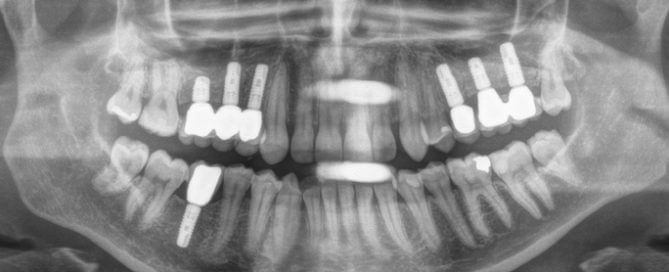

Implantologie